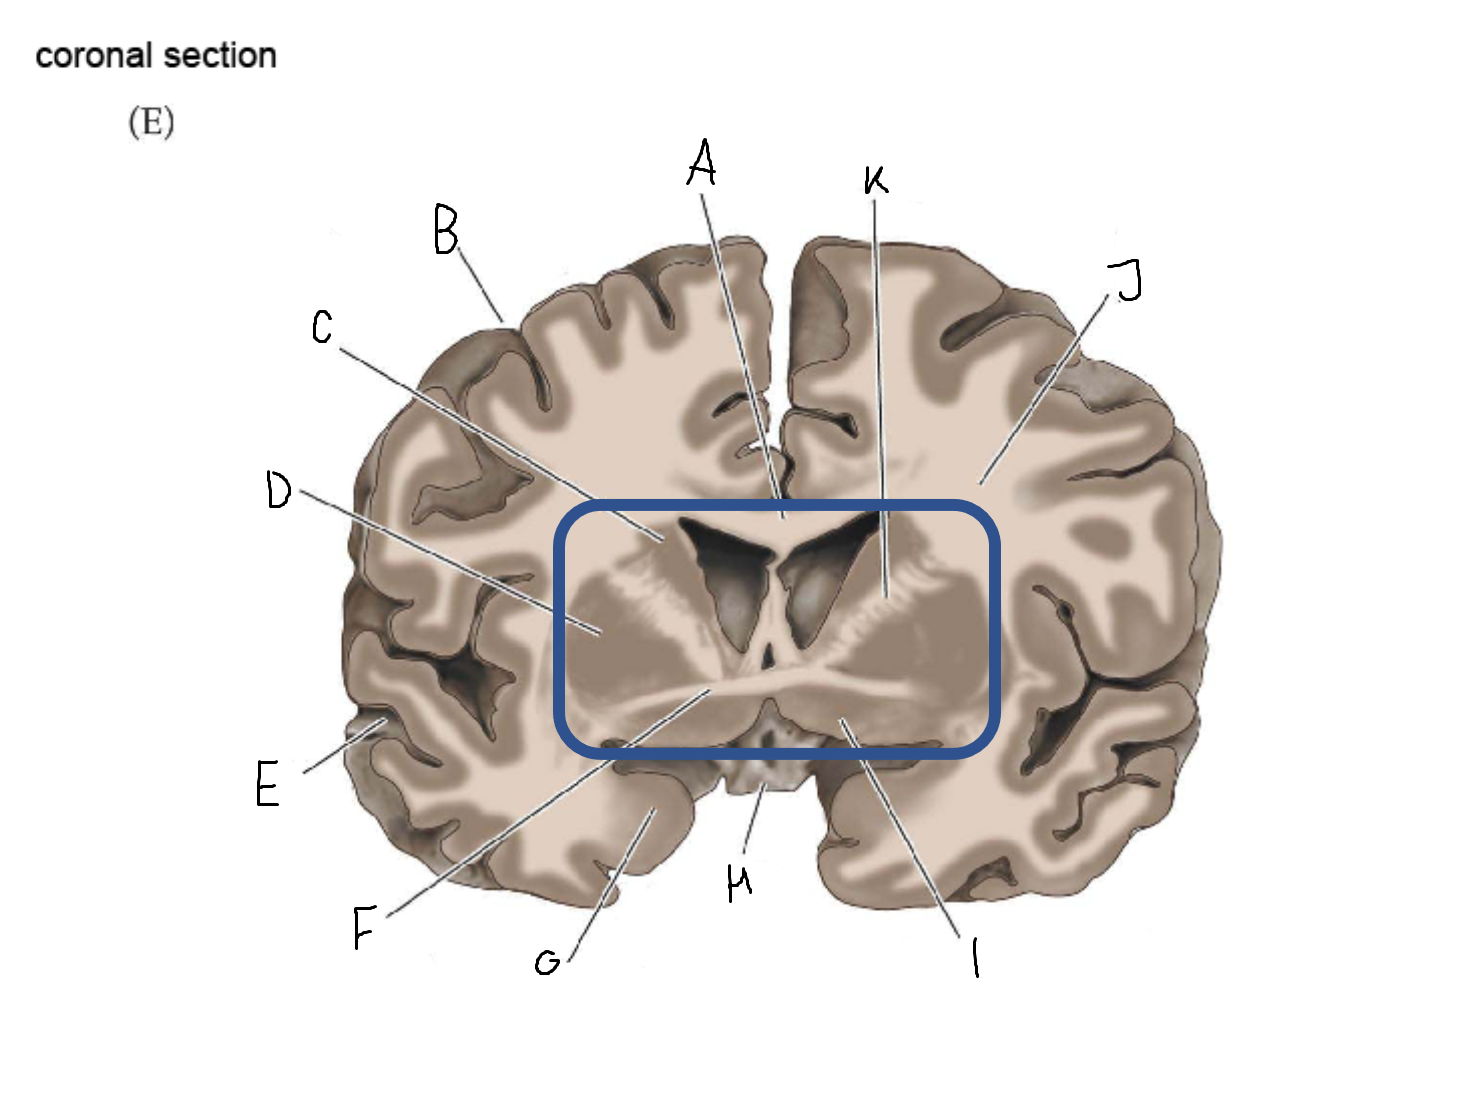

A

corpus callosum

B

lateral ventricle

C

internal capsule

D

third ventricle

E

tail of caudate nucleus

F

lateral ventricle

G

hippocampus

H

mammillary body

I

fornix

J

globus pallidus

K

putamen

L

caudate

M

thalamus

N